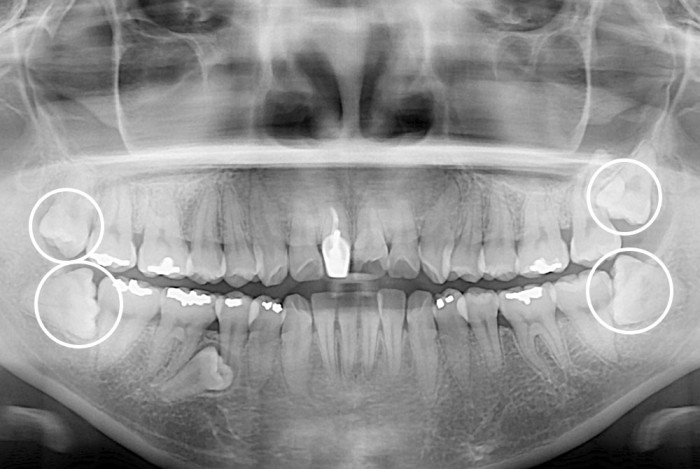

[사랑니] 사랑니

PX20200226_172545_0402_00000000.jpg

치료후 : 2020-02-26

세종치과는 구강악안면외과학 박사이신 원장님이 발치하는 치과입니다.